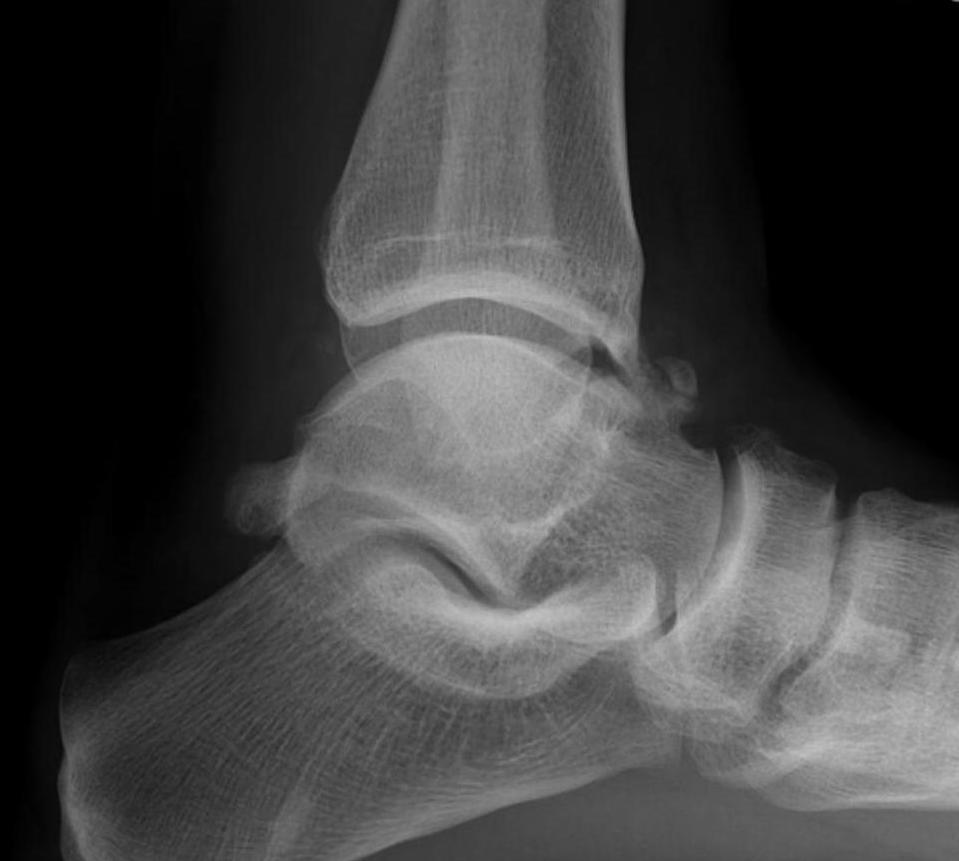

Xray

Ranges from anterior spurring to severe OA

80% of post-traumatic OA is varus

Takakura classification

| 1 | Early sclerosis and formation of osteophytes |

| 2 | Narrowing of the medial joint space |

| 3A | Obliteration of the medial joint space with subcondral bone contact |

| 3B | Obliteration of joint space over roof of talar dome, with subchondral bone contact |

| 4 | Obliteration of joint space with complete tibiotalar contact |

Type 1: Anterior spurs

Type 3A: Obliteration of medial joint space Type 3B: Obliteration medial joint space plus tibio-talar contact with varus

Type 4 complete obliteration